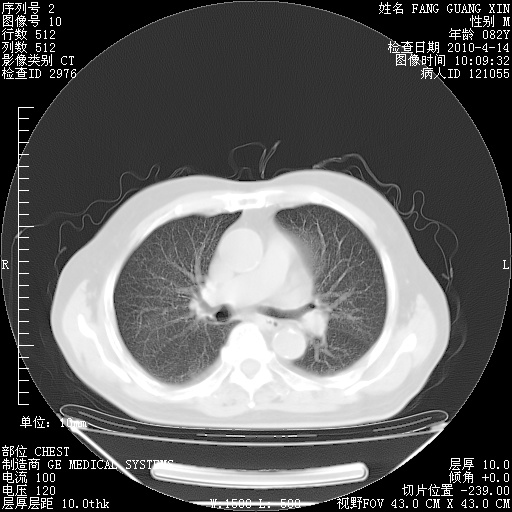

4月14日肺部CT

23.JPG

24.JPG

25.JPG

26.JPG

肺部CT平扫未见异常。